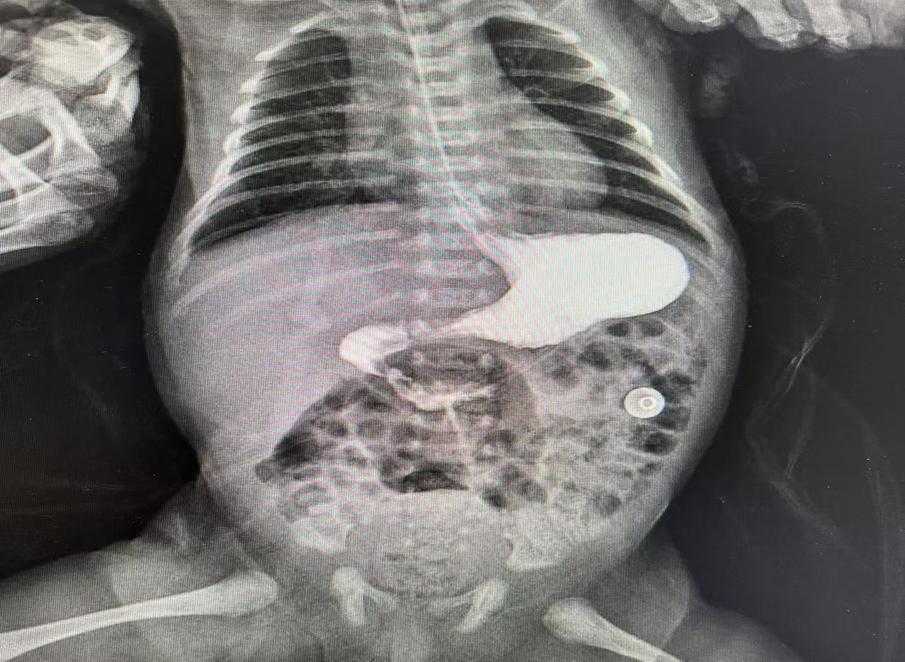

圖片10.jpg

術后復查十二指腸已通暢